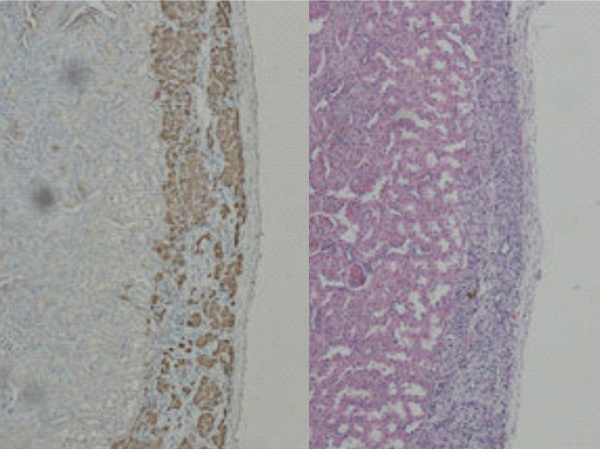

上圖為腎被膜下移植的大鼠胰島HE和免疫組合化染色結(jié)果。